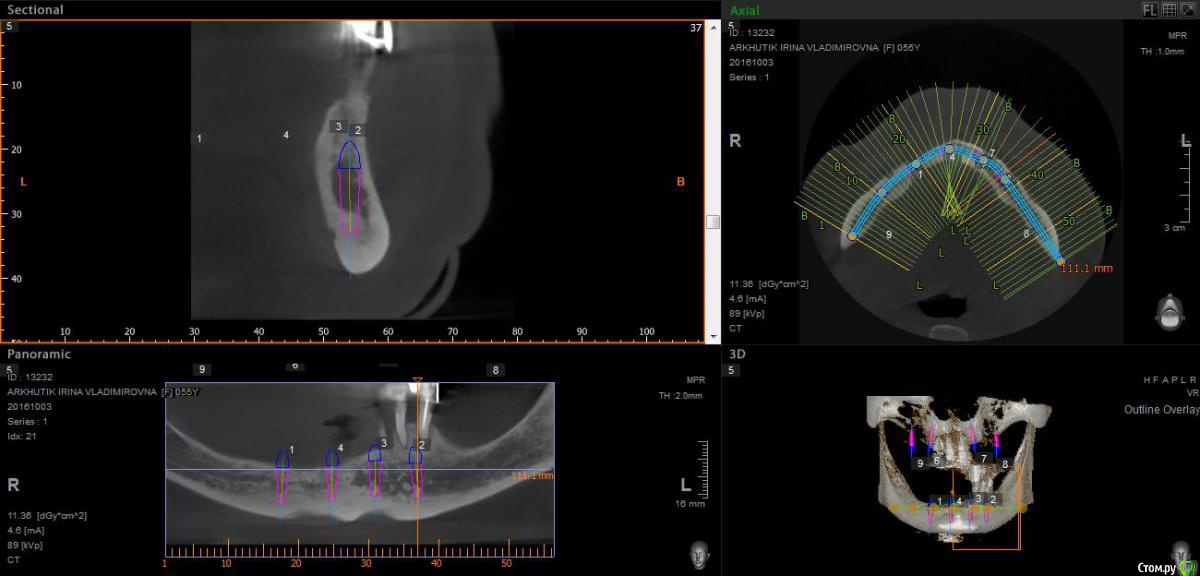

Rusty Опубликовано 5 октября, 2016 Поделиться Опубликовано 5 октября, 2016 Добрый день. К ортопеду обратилась пациентка 55-60 лет с такой ситуацией. Пришла с дочкой, дочь с мамой настаивали на несьемной конструкции, ортопед отправил на кт и вот. Не хочу планировать ей много хирургии, оцените и мой план пожалуйста и буду рад услышать советы по реабилитации пациента. По сути да) просто искал место куда есть возможность поставить, ортопед говорит тогда балка либо локаторы Ссылка на комментарий

Nazim_NV86 Опубликовано 5 октября, 2016 Поделиться Опубликовано 5 октября, 2016 На н/ч балка? Какие измерения в дист отделах? На в/ч мало четырёх. По три бы. Ссылка на комментарий

Rusty Опубликовано 5 октября, 2016 Автор Поделиться Опубликовано 5 октября, 2016 На н/ч балка? Какие измерения в дист отделах? На в/ч мало четырёх. По три бы.На н/ч балка, в дистальных отделах над каналом около 3мм. На вч условий для установки больше 4 не нашел) Ссылка на комментарий

Nazim_NV86 Опубликовано 6 октября, 2016 Поделиться Опубликовано 6 октября, 2016 Попробуйте на вч поискать ещё возможность хотя бы по Палаччи поставить. Ссылка на комментарий